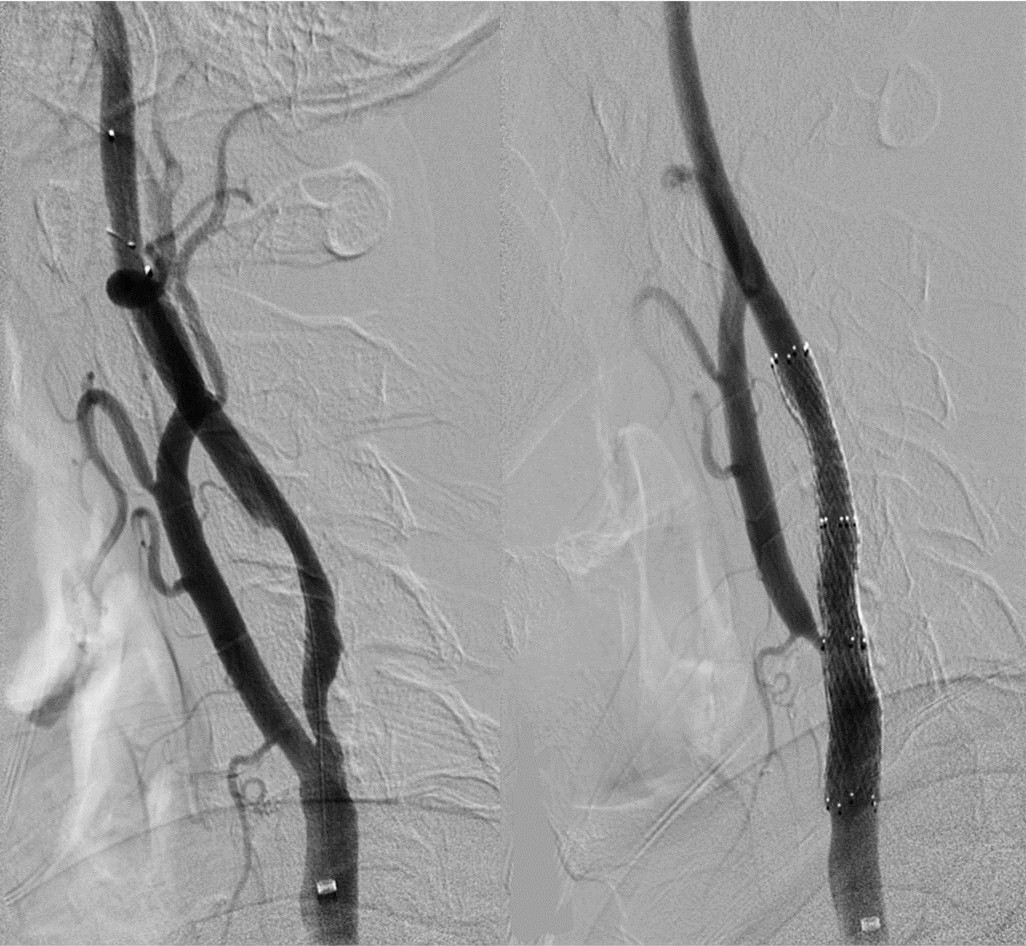

术前CTA提示王先生的主动脉弓形为“牛”型解剖变异(左侧颈总动脉从无名动脉发出,图1),颈总动脉起始部及颈内动脉均存在斑块狭窄,为手术增加了难度,经过仔细讨论分析病情,血管外科吴巍巍主任、赵克强教授决定“另辟蹊径”,从患者右上肢入路,实施微创颈动脉支架手术,同期解决颈总及颈内动脉两处病变。经过充分的术前准备,吴巍巍主任和赵克强教授在麻醉科医师的保驾下联手为王先生安全实施颈动脉微创支架植入术(图3、4),避免了王先生今后再次发生严重的脑卒中事件。术后返回病房,精准调控血压、心率,5天后王先生顺利康复出院。

图2-3 颈内-颈总动脉植入支架

图2-4 颈总起始植入支架